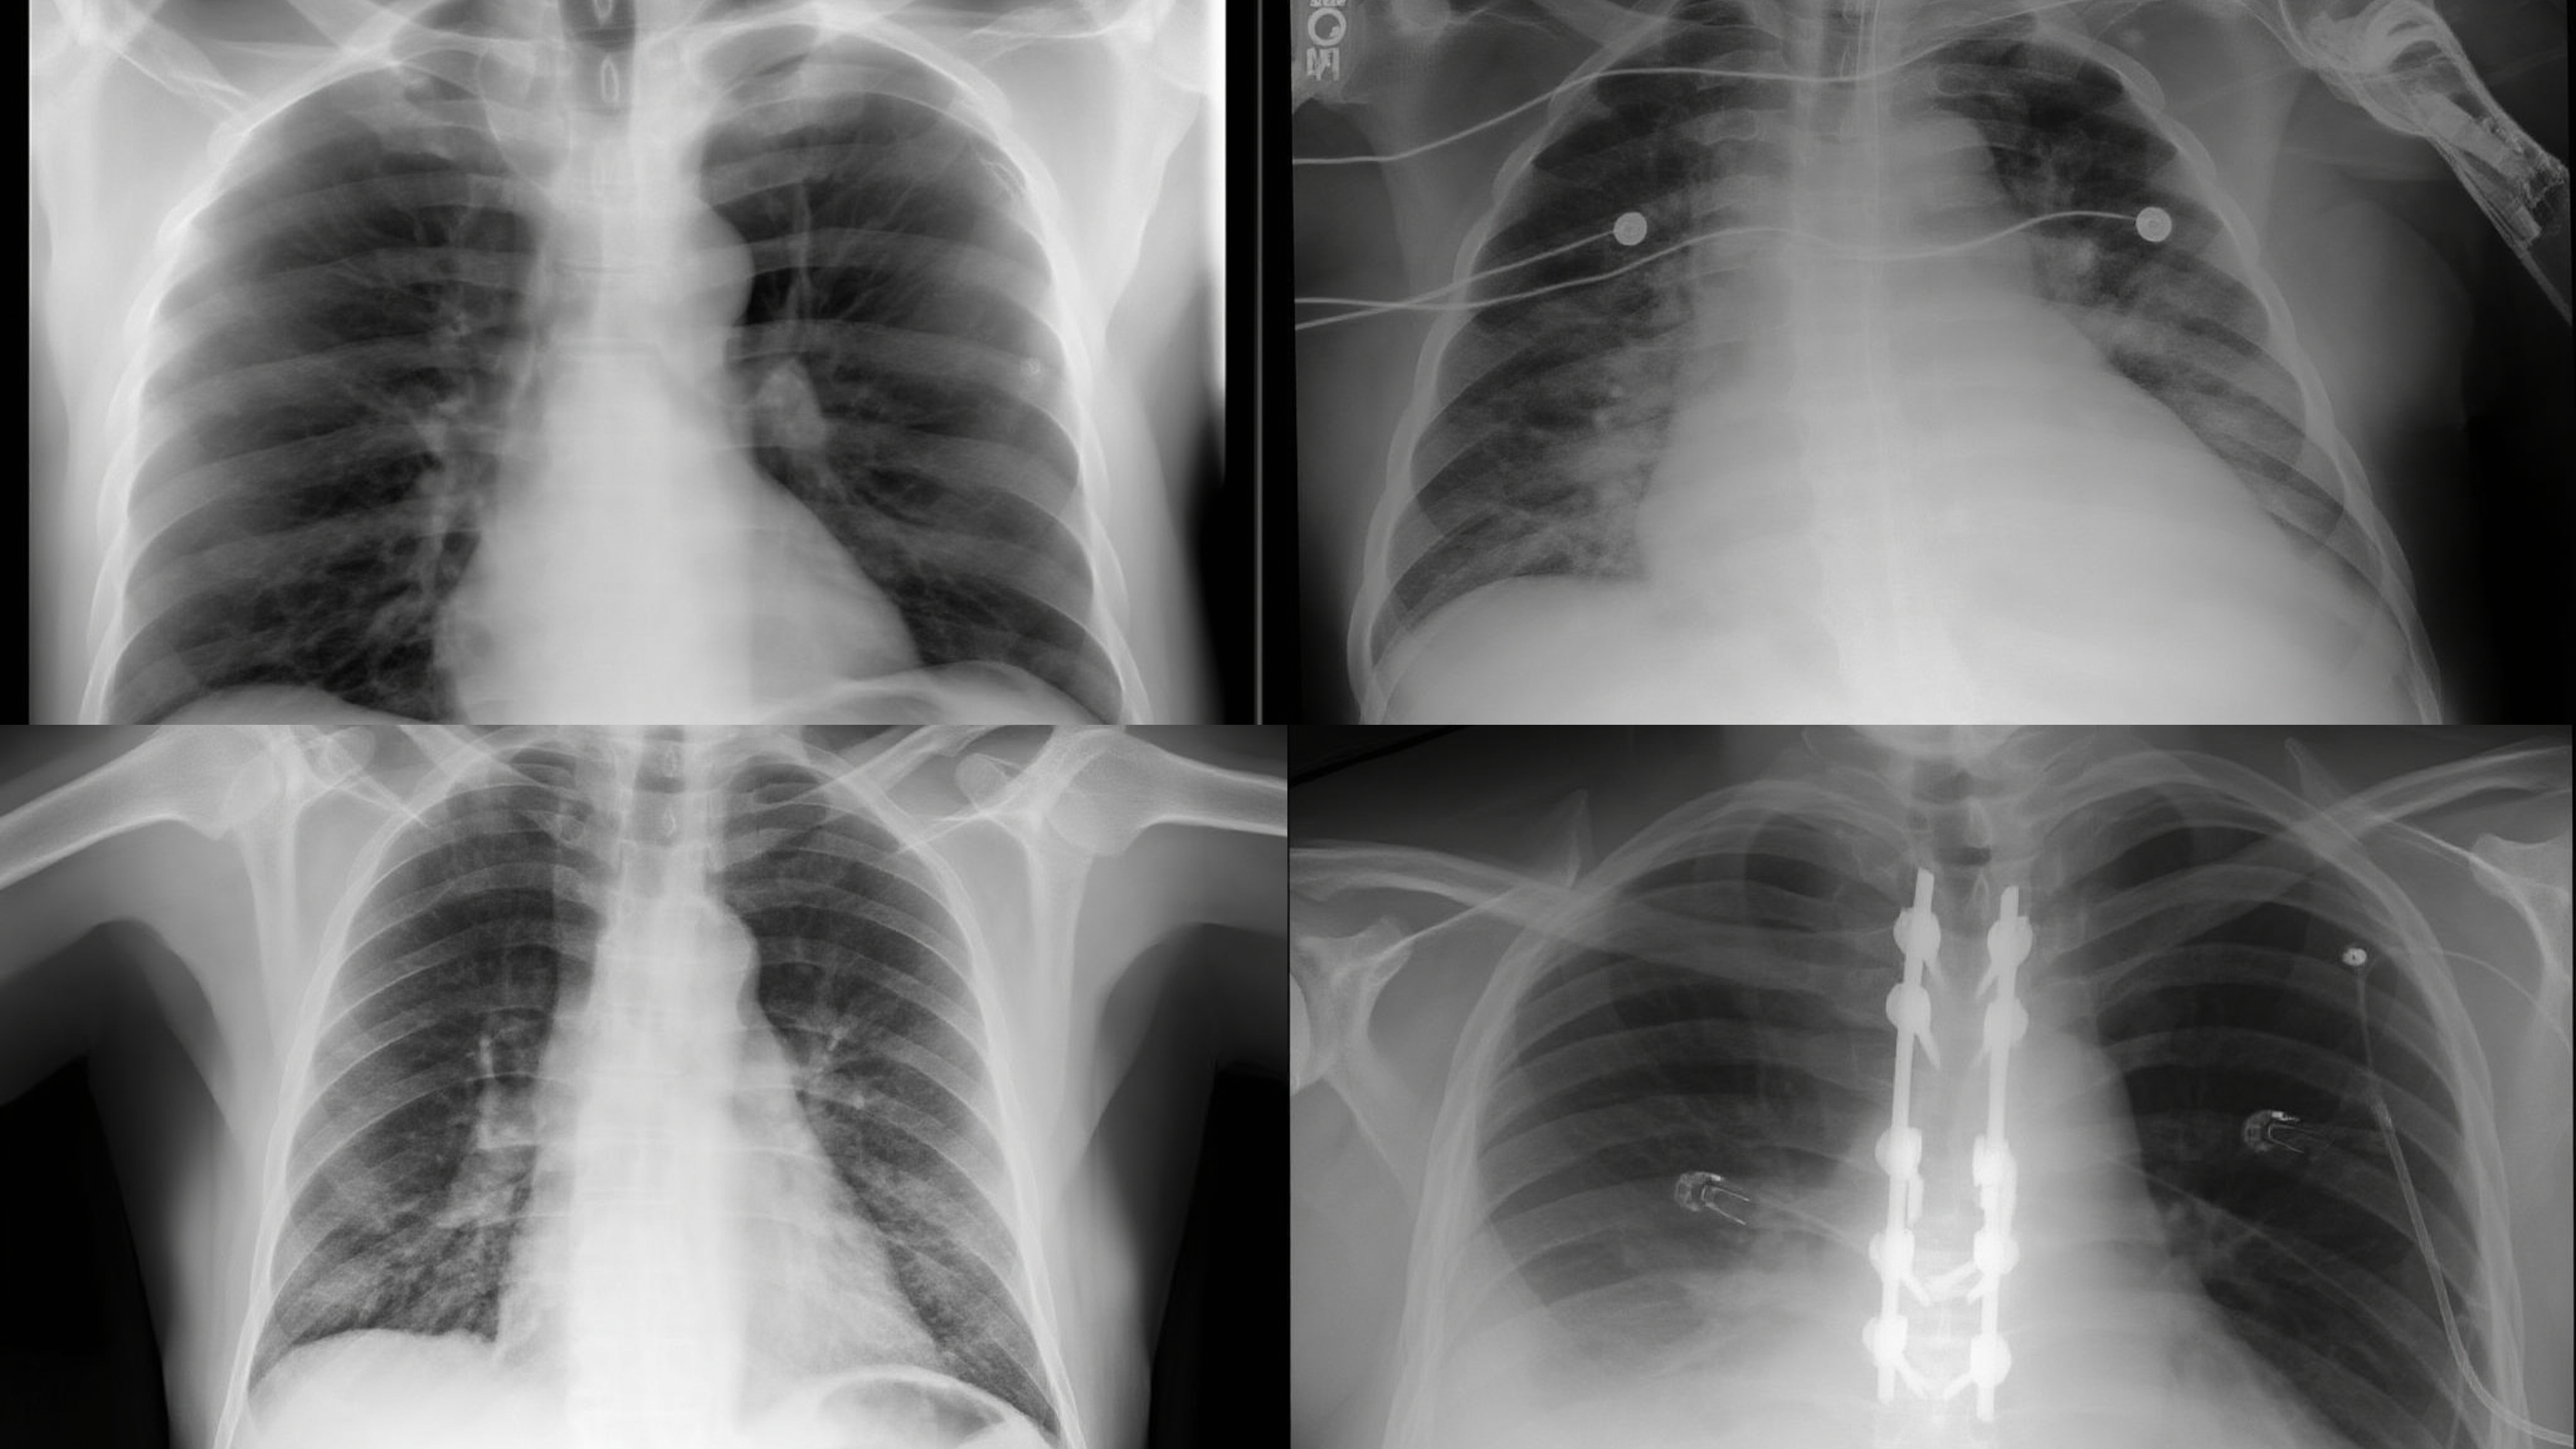

Chest X-Ray (CXR)

Chest X-Ray